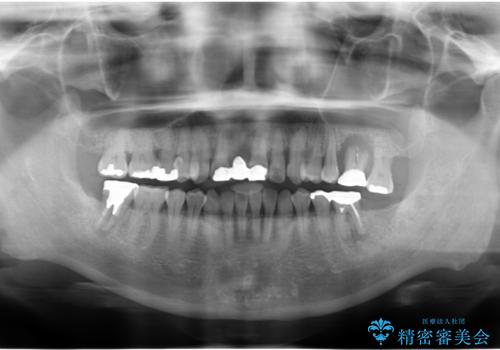

歯周病に対する全体治療

- 近医で「重度の歯周病です、入れ歯にする必要がある。」、と言われ入れ歯以外の方法がないか相談にみえられました。

再生治療、歯周外科を行うことで歯周病治療を行い、残すことのできる歯の歯周環境を整える。

残すことのできない歯は抜去したのち骨造成を含めたインプラント治療を行い、しっかりとした咬合関係を確立していきます。

治療期間はかかりましたが、しっかりと歯周病治療・インプラント治療を行ったおかげで歯周病の状態は非常に良くなり、安定した咬合関係を確立することができました。